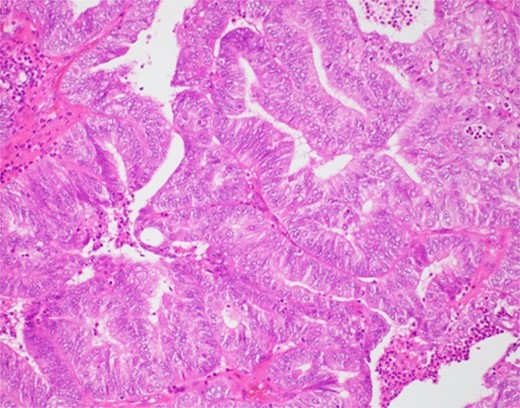

The histological findings with hematoxylin-eosin stain (H&E) revealed a cystic lesion with a very small and relatively dense stroma under the epithelium in the left paratubal region (Fig. 3). This stroma is CD10 positive in a small portion, suggesting the possibility of endometriosis (Fig. 4). Moreover, adenocarcinoma is arises from this cyst (Figs 5 and 6). There was no disseminated lesion in bilateral adnexa and uterus.

With these histological findings, we diagnosed the tumor as an endometrioid carcinoma arising from the paraovarian cyst.